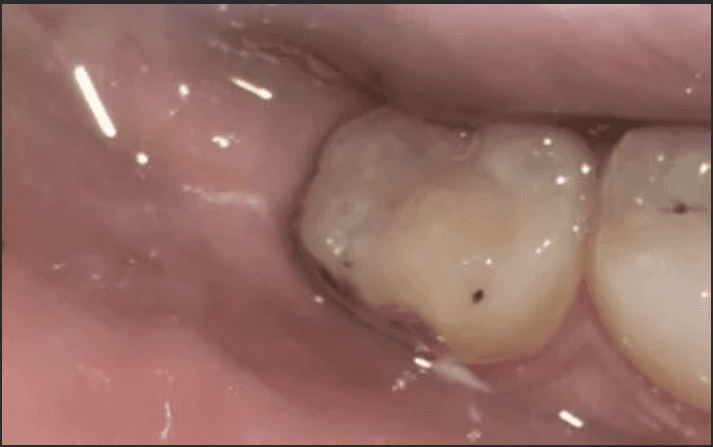

A 25-year-old woman accidentally bit into the thin collar of gum sitting over her lower right wisdom tooth and wanted to consider extraction. Despite being a wisdom tooth, it was a functional tooth with an opposing wisdom tooth to bite against. It was an issue with overlying gum, rather the wisdom tooth itself. After removing the collar of gum, it recovered well without recurrence and she has managed to keep the wisdom tooth to present day without any further issues.

1 Month After